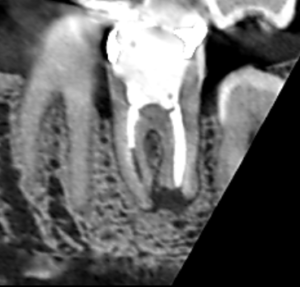

下顎大臼歯の矢状断のCT画像です。

矢印の先に膿の影がみられます。遠心根の先が吸収され、平らになっています。

膿が長くあった可能性が高いケースです。

もう既に根尖孔外感染を起こし治りにくい膿に代わっている可能性があります。